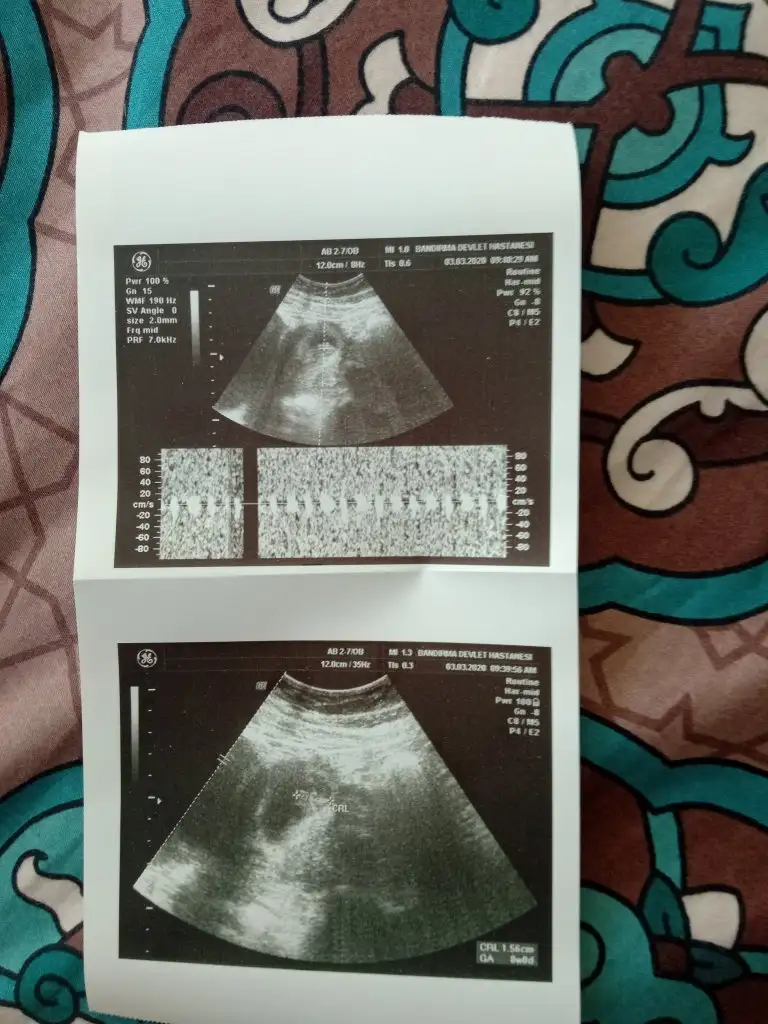

Dr +getirmiş sanki erkek gibi gibi siz 12 13 hafta usg de paylaşın emin olamadımMerhabalar bizde burda 11 haftadaydik bizede tahmin edebilirmisiniz rica etsem ❤

kıza benzettimMerhabalar bizde burda 11 haftadaydik bizede tahmin edebilirmisiniz rica etsem ❤

Teşekkür ederim önce sağlık tabiki ama gönlüm den de kız geçiyorkıza benzettim